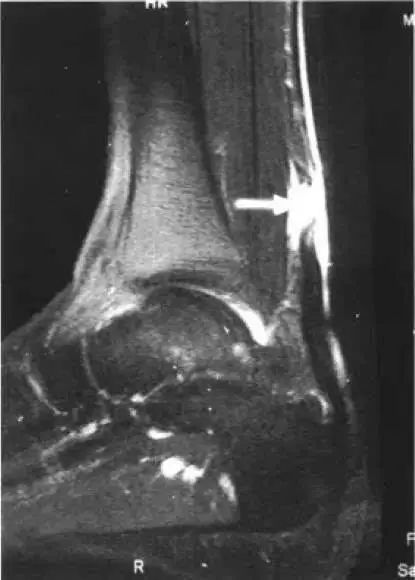

正后方看,可以看到粗黑长的跟腱再中间变得不连续了

白色箭头是跟腱 三角是断裂处

白色箭头是跟腱的断裂部位